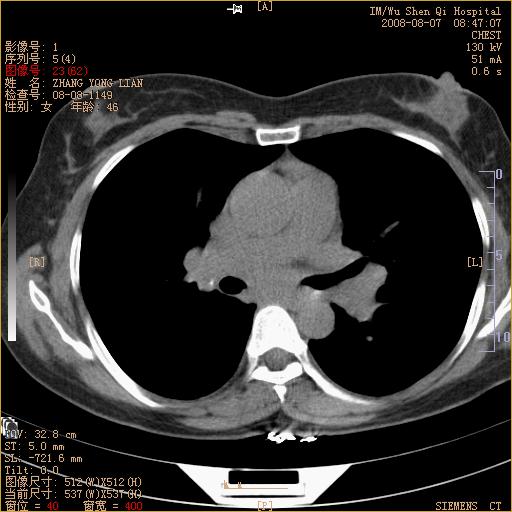

标题: CT15050:女,46岁,咳嗽胸痛一月余 [打印本页]

脾脏低密度结节转移不排除。

1)考虑左肺下叶后基底段周围型肺癌伴纵隔淋巴结转移。2)脾内低密度灶,性质待定;不排除转移瘤可能。

恶性度很高的肺癌.